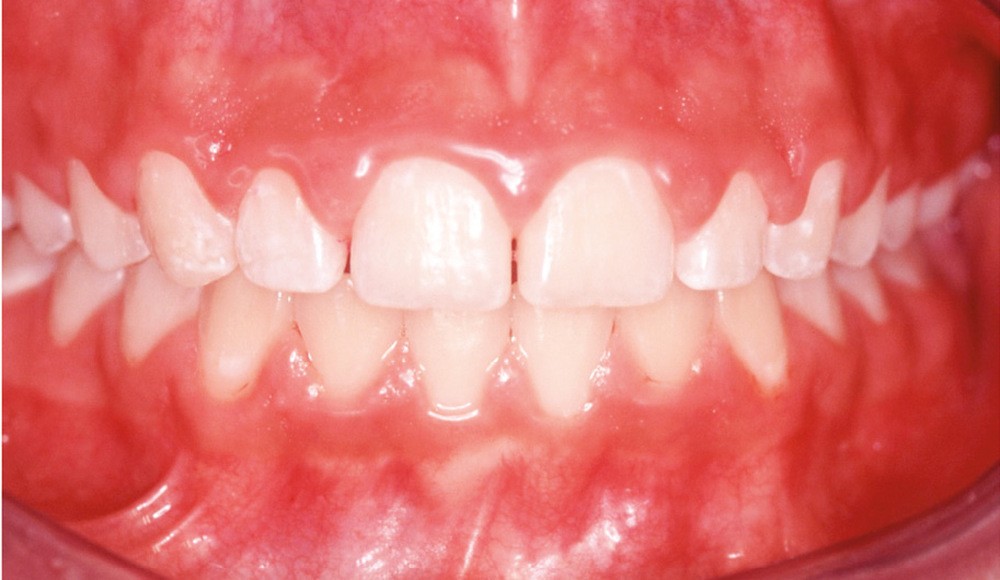

Les modifications hormonales à mettre en relation avec l’hygiène bucco-dentaire, les paramètres socio-économiques, l’âge précoce de la grossesse ainsi que l’augmentation du grignotage pourraient augmenter la prévalence des caries dentaires chez la femme enceinte. Ces patientes sont régulièrement sujettes à des envies multipliant le nombre de prises alimentaires souvent très riches en sucre. Ces apports sucrés, associés à la baisse du pH salivaire lors de la grossesse, entraînent un déséquilibre du cycle déminéralisation et de reminéralisation. Le risque carieux peut être augmenté, ainsi que la susceptibilité à l’érosion dentaire accrue par les vomissements et/ou les reflux gastro-œsophagiens [2]. L’action hormonale peut également avoir des répercussions sur les tissus parodontaux. La gingivite gravidique observée sur plus d’une femme enceinte sur deux, constitue une réponse inflammatoire de la gencive exacerbée par la présence de plaque bactérienne, et favorisée par l’augmentation des taux d’œstrogène et de progestérone [3] (fig. 1). 5 % des futures mères développeront un épulis, dont l’étiologie reste méconnue (fig. 2) [4].